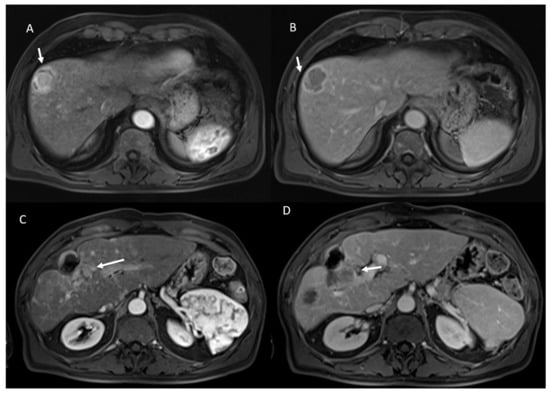

- 53 showed non rim APHE and 60 hypointense SI during arterial phase (Figure 5).

- 3 showed peripheral washout appearance and 110 hypointense SI in portal phase (Figure 5).

- 113 lesions were hypointense in equilibrium phase.

- 98 showed iso-hypointense SI in T2-W and 15 iso-hyperintense SI in T2-W (Figure 6).

- 100 showed hyperintense SI in T1-W and 113 targetoid appearance.